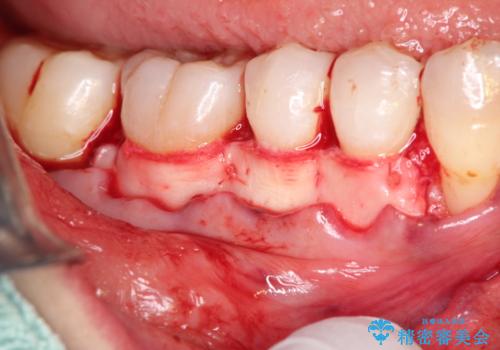

- 昔に受けた矯正治療がきっかけで歯肉が下がってしまった事を主訴として来院された患者様です。

結合組織移植術を行う方法を提案しましたが、傷口が口蓋にもできるのが嫌だとのことで、代替案としてバイオマテリアルを併用した根面被覆術を計画致しました。

治療対象部位は右下4,5,6番の3本です。